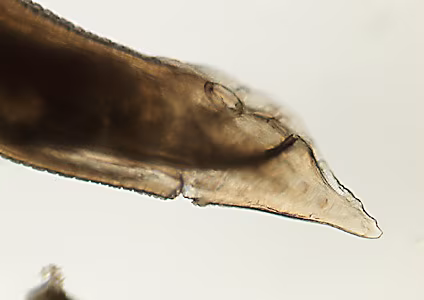

A state public health laboratory received three worms from a regional commercial laboratory for identification. The public health laboratory submitted the worms to the CDC/DPDx Team for diagnostic assistance. The submission form indicated that how and where the worms were collected was not provided by the commercial laboratory. Figure A shows all three worms for gross presentation and size determination. A dissecting microscope was used to observe morphologic features. Figures A and B shows two separate focal planes of the anterior of one worm; Figures C, D and E show three aspects of the tail. What is your diagnosis? Based on what morphologic features.

Figure D